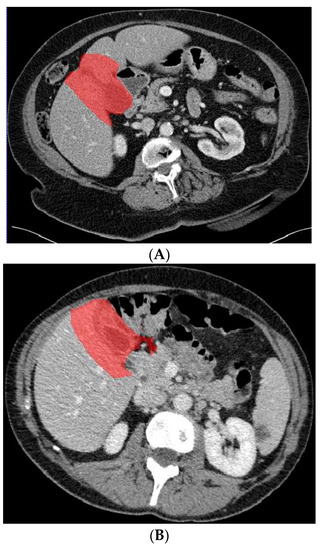

Figure 3.

Axial CT slice (A) with an example of benign gallbladder disease (adenomyomatosis, encircled in (B)) and subsequent segmented gallbladder (C).